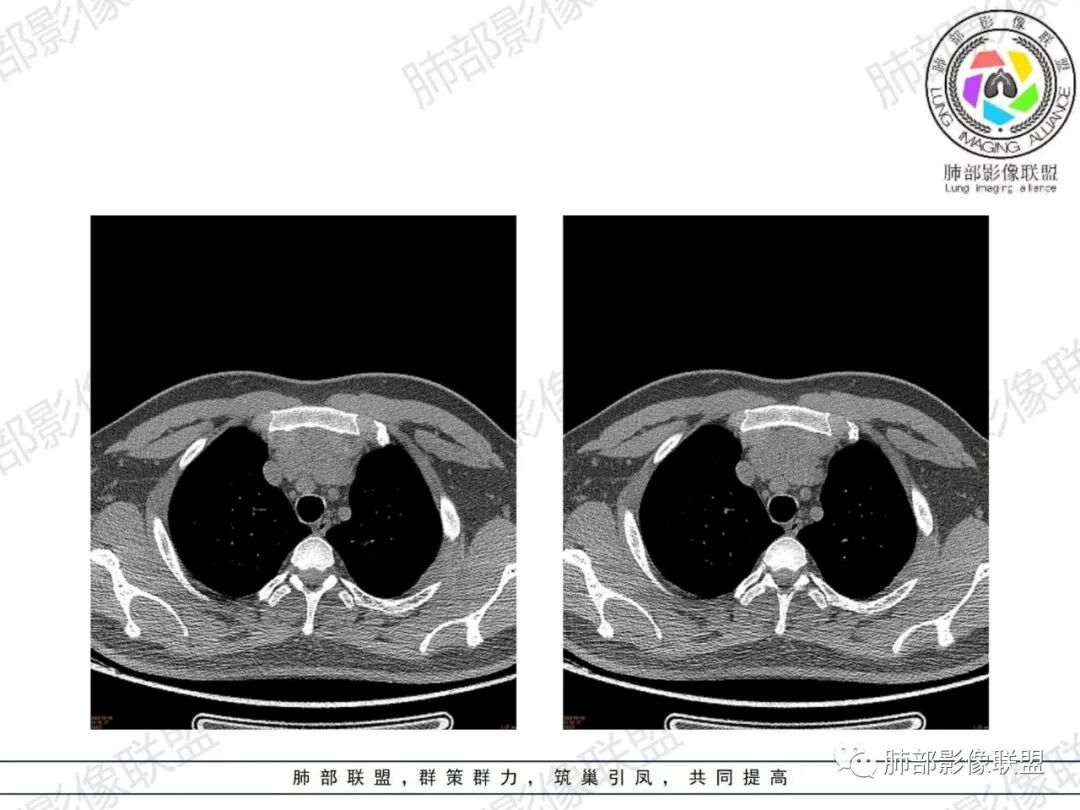

简·爱:年轻男性,26岁,小于30岁 (黄勇老师说小于30岁,诊断胸腺瘤要慎重),双下肢无力一个月,亚急性病程,前纵隔胸腺区不规则软组织密度灶,密度较均匀,无明显钙化和坏死、出血,隐约见条状低密度分隔影和斑点装脂肪密度,病灶比较软,浅分叶,胸腺轮廓基本还在,不知道强化怎么样,考虑胸腺增生,鉴别,胸腺瘤瘤,淋巴瘤,生殖细胞瘤。

King:确实在影像不足的情况下,年龄和症状是重要考量因素。影像形态膨胀不足,钻隙明显,密度似夹脂肪,首先胸腺增生,其次淋巴瘤,胸腺瘤或癌不首先考虑了。

毛勤香:青年男性,26岁,肌无力,病灶贴着主动脉,有结节感,感觉含脂,首先考虑胸腺增生,鉴别胸腺瘤,淋巴瘤,生殖来源肿瘤,得看一下重建和增强。

郑氏刀刀:年纪这么轻,边缘膨隆感局部较弱,质地软,中央有脂肪浸润样密度,伴肌无力,常规考虑胸腺增生,鉴别淋巴瘤(密度较高,均匀),胸腺瘤(密度较高,无脂肪浸润,质地较硬),精原细胞瘤(类似淋巴瘤,可坏死)。

被强煎的蛋.¢?:青年男性,胸骨后前纵隔内胸腺增大,厚度增加,边缘光整膨胀力弱,分叶浅,与胸骨及主动脉弓和心前缘接触面较宽,与周围正常结构分界清楚,无淋巴结肿大及胸膜、心包受累等。拟考虑胸腺增生。

弥漫性增大,两缘对称,质地柔软,部分淋巴性胸腺增生的大小正常;形态保持其正常形态,呈类圆形、梨形,边缘光滑,可呈浅分叶

密度:

密度均匀,呈肌性密度,偶见细小钙化,其内有脂肪浸润样密度影

1、年轻男性,双下肌乏力,胸部CT提示前纵隔胸腺区病变,应当怀疑胸腺增生或胸腺瘤导致的重症肌无力。

2、前纵隔梨形软组织密度影,与正常胸腺形态一致,为胸腺弥漫性增大,两缘匀称,质地柔软,未见明显膨隆,其内可见脂肪浸润影,与周围结构分界清楚,再加上病人年龄,需要高度提示胸腺增生(淋巴滤泡样增生型)。胸腺瘤一般无脂肪浸润,质地较硬,呈结节或肿块状,且发病年龄较大。B2B3型肿块边界不清,可侵犯临近组织脏器,B3可胸膜转移,胸腺癌可引起纵隔淋巴结及远处转移。